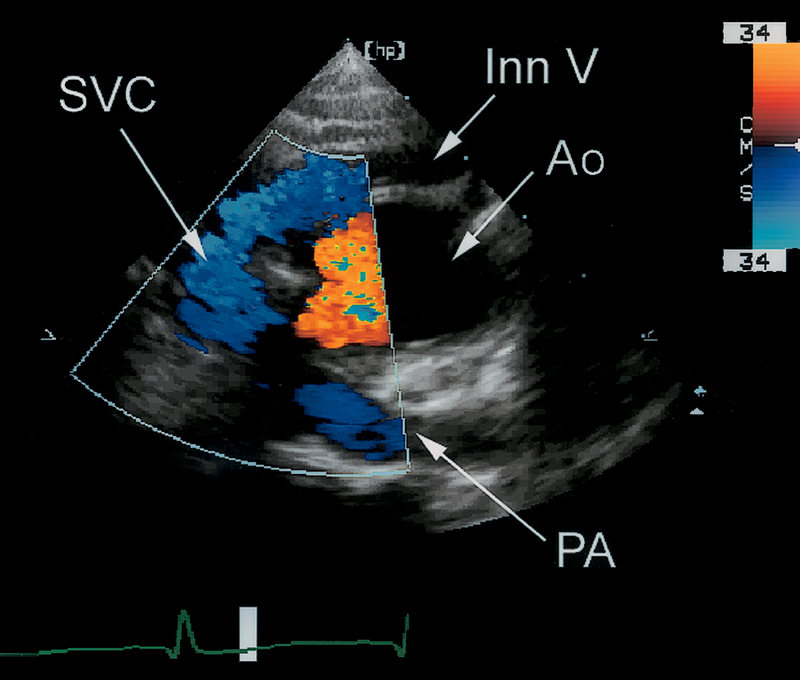

فحوصات تشخيصية لبعض امراض القلب والشرايين التاجية